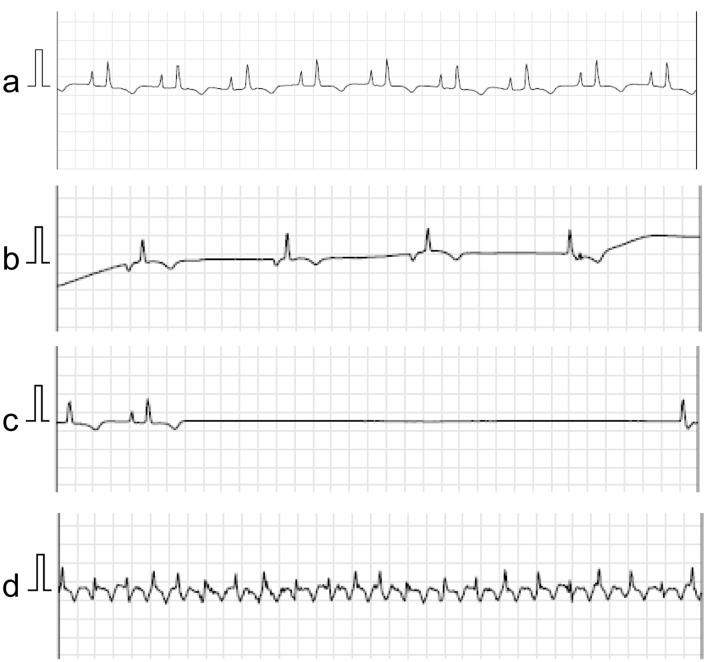

Primary cardiac lymphoma is a rare, often fatal malignancy that can cause disorders of conduction depending on tumor location. We report two cases with sick sinus syndrome and atrial flutter secondary to primary cardiac lymphoma originating from the right atrium. One case required pacemaker implantation in the chronic phase after complete remission of lymphoma, and the other case in the acute phase when cardiac mass occupied the right atrium. Depending on the disease activity of lymphoma including its size, growth rate, and degree of invasion, the clinical course of sinus node dysfunction varies between each patient. In patients with conduction disorders, we suggest that long-term cardiac monitoring is necessary not only at onset but also after complete remission of lymphoma.

原发性心脏淋巴瘤是一种罕见且通常致命的恶性肿瘤,根据肿瘤位置可导致传导障碍。我们报告了两例因起源于右心房的原发性心脏淋巴瘤继发病态窦房结综合征和心房扑动的病例。一例在淋巴瘤完全缓解后的慢性期需要植入起搏器,另一例在急性期心脏肿块占据右心房时需要植入。根据淋巴瘤的疾病活动情况,包括其大小、生长速度和侵袭程度,每位患者窦房结功能障碍的临床过程各不相同。对于有传导障碍的患者,我们建议不仅在发病时而且在淋巴瘤完全缓解后都有必要进行长期心脏监测。